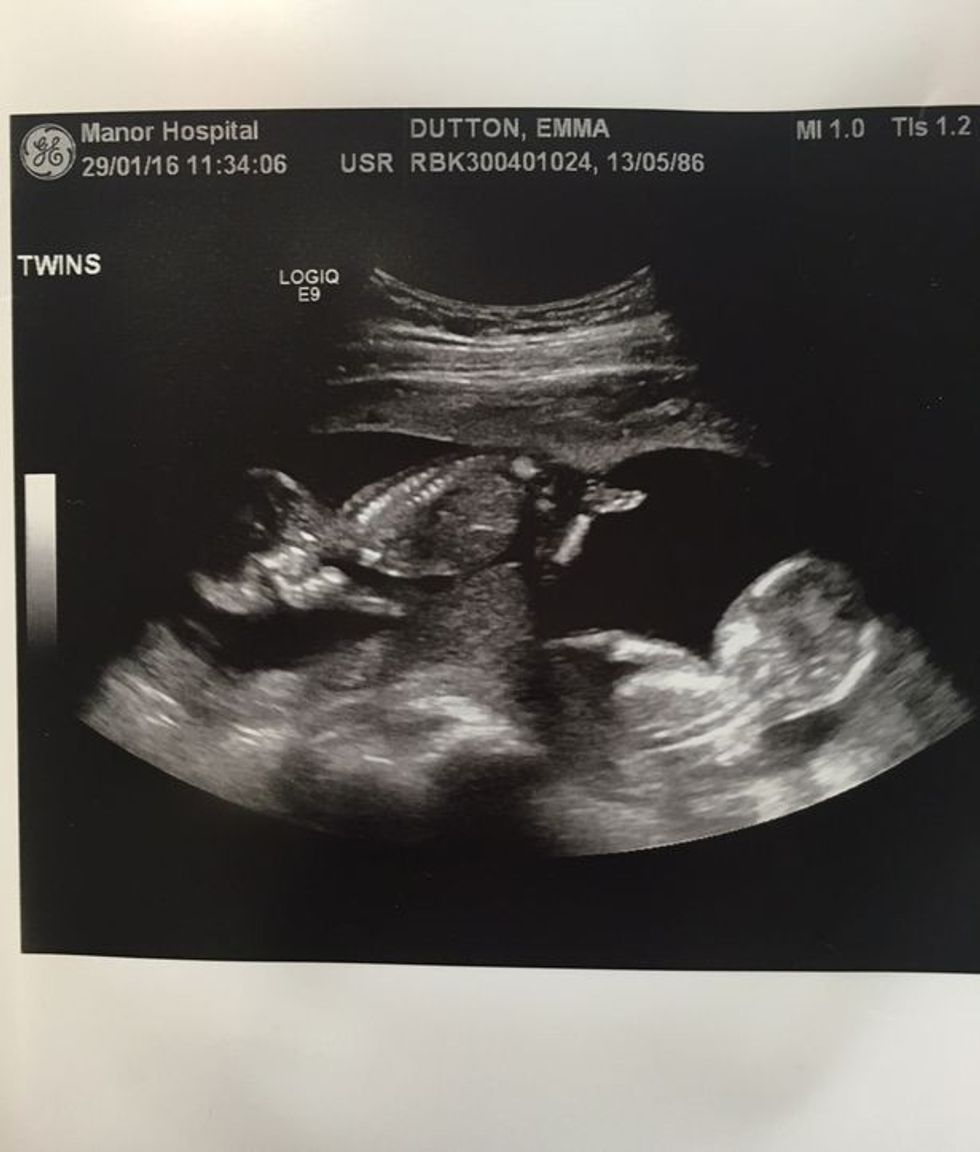

Megjithatë, gëzimi i këtij çifti nuk zgjati shumë – pasi e kuptuan përmes ultrazërit se diçka nuk është në rregull.

Pasi shikuan në ekran, mjekja ua kumtoi lajmin se njëri nga djemtë binjakë është duke vuajtur nga një sëmundje e rrallë që po i rrezikonte jetën.

Dy javë më vonë, në javën e 20-të të shtatzënisë, frika e tyre më e madhe doli të jetë e vërtetë, kur mjekët u thanë se njëri nga fëmijët në barkun e Emmas ka vdekur.

Këtë gjë e vërtetuan në ultrazë, kur edhe e panë se nuk kishte lëvizje të njërit fëmijë por as rrahje të zemrës.